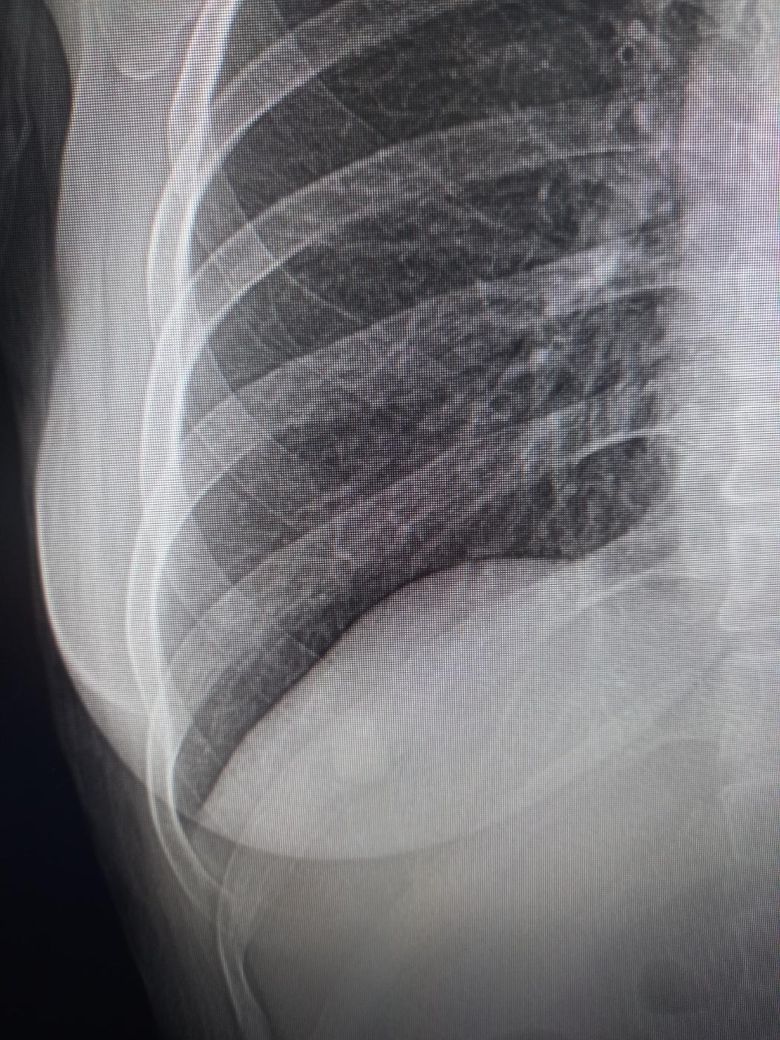

72세 흉부 엑스레이 사진 봐주세요.

전후 사진입니다. 전 사진은 약 1년전 사진이고요 오늘 찍은거랑 비교해봤을때, 선생님께서 우측 하복부 늑막변형 소견이라 큰병원가서 흉부CT찍어보라는데요 위암1기 (1기중에서도 초기) 전절제 한지 18개월차인데 전이일 수 있나요? 평상시 통증이나 체력 저하 등 달라진건 전혀없으시고 식사,운동 잘하십니다

• 2번 째 사진

모니터를 핸드폰으로 찍으셨는지 올려주신 사진의 경우 해상도가 떨어집니다.

우측 하복부 늑막변형 소견에 대해서는 좀 더 자세한 검사를 위해 흉부CT 검사를 권합니다.

초기 위암 병변을 전절제 한 경우 위 내시경 검사의 확인이 필요하겠으나 전이 가능성은 낮을 것 같습니다.